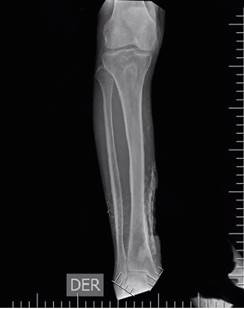

Inicialmente consultó en el hospital local, donde iniciaron manejo antibiótico con clindamicina y ampicilina-sulbactam, con posterior exposición ósea y miasis, por lo que remitieron a una institución de mediana complejidad, donde administraron una dosis única de ivermectina, con curación completa de la miasis. Sin embargo, hubo persistencia de la exposición ósea por lo que se decidió remitir a una institución de alta complejidad para manejo multidisciplinario, con el diagnóstico de sospecha de osteomielitis de tibia. Al ingreso a la institución se realizó una radiografía AP y lateral de la pierna derecha donde se apreciaba una zona calcificada en la región medial de la extremidad, la cual se puede observar en las Figuras 2 y 3.

Figura 2 Radiografía AP de pierna derecha.

Figura 3 Radiografía lateral de pierna derecha.